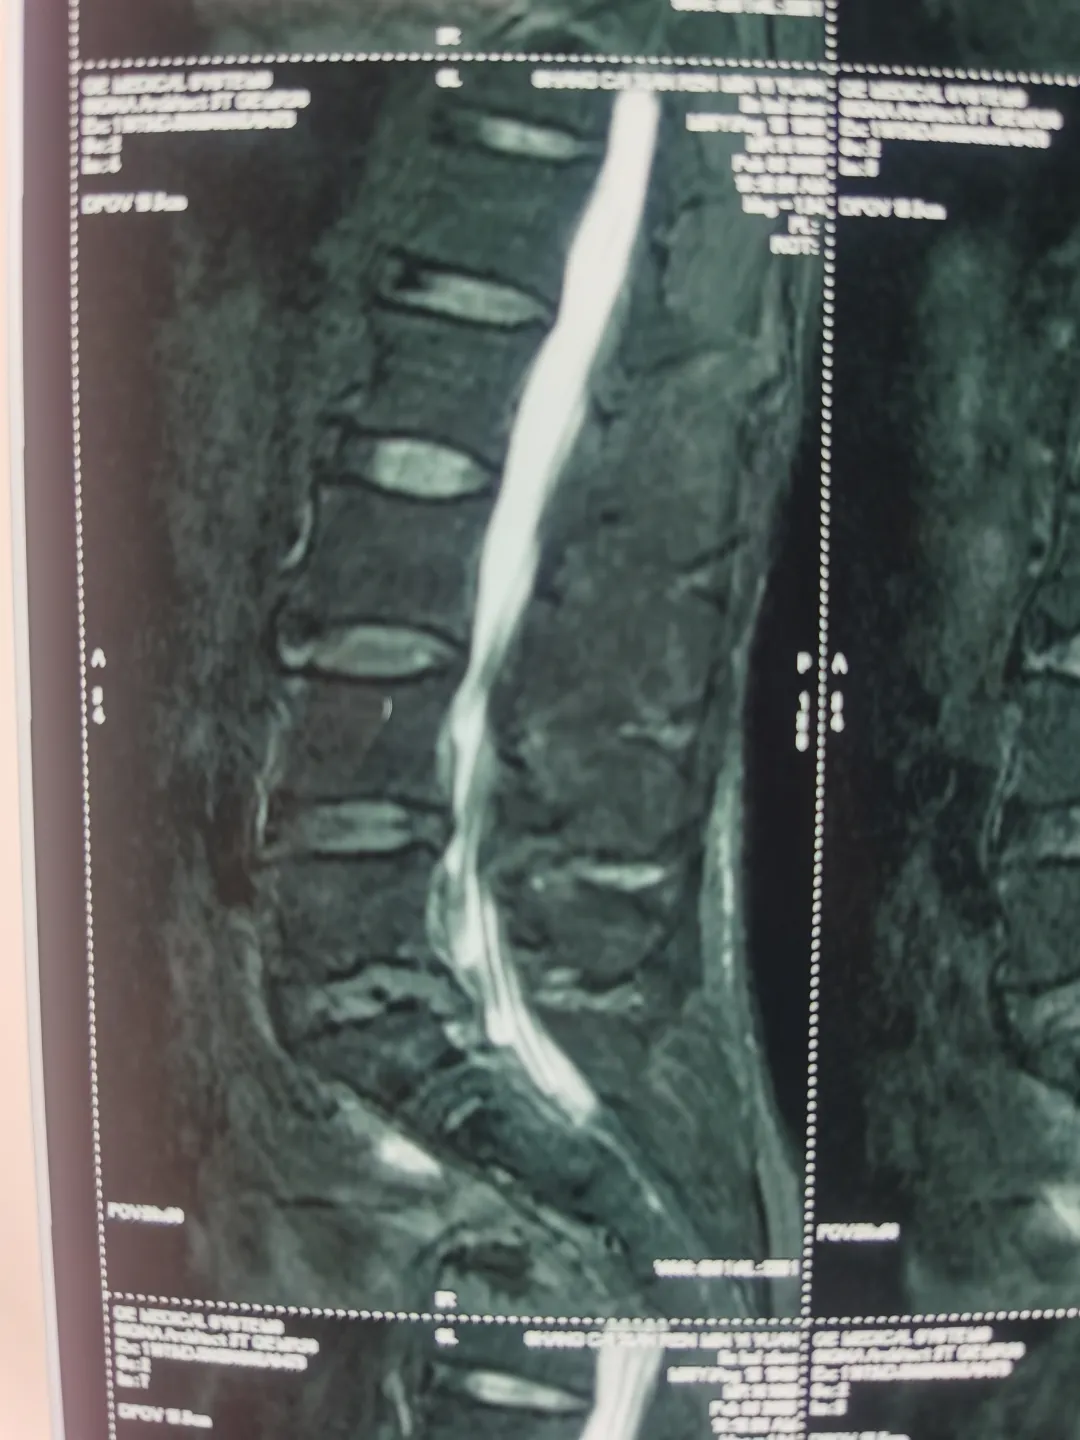

今年55歲的羅大叔(化名)2年前出現(xiàn)腰部疼痛,呈間斷性,休息后可緩解,前段時(shí)間在干活后又出現(xiàn)了腰部疼痛,同時(shí)伴有右下肢疼痛、麻木,嚴(yán)重影響生活質(zhì)量,為求進(jìn)一步治療,便來到駐馬店廣濟(jì)心血管病醫(yī)院暨武漢亞洲心臟病醫(yī)院豫南醫(yī)院,劉主任接診后,為患者進(jìn)行詳細(xì)的檢查,診斷為腰4-5、腰5-骶1椎間盤突出,腰椎退行性變。

圖片

羅大叔住院后,劉主任帶領(lǐng)團(tuán)隊(duì)經(jīng)過周密的術(shù)前討論和規(guī)劃,結(jié)合患者意愿,決定為患者實(shí)施內(nèi)鏡下微創(chuàng)手術(shù),劉主任表示:這個技術(shù)與傳統(tǒng)開刀手術(shù)相比,它是借助天然解剖間隙建立微創(chuàng)工作通道,解除神經(jīng)壓迫,對椎旁肌肉損傷較小,且能夠保留完整的脊柱結(jié)構(gòu),維持了術(shù)后脊柱的穩(wěn)定。